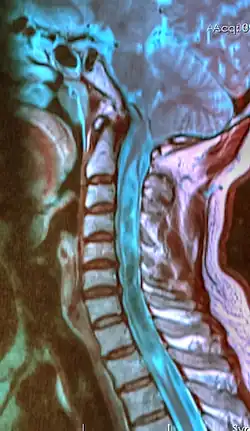

A sagittal FLAIR MRI scan, from a patient with an Arnold–Chiari malformation, demonstrating tonsillar herniation of 7 mm. | |

Diagnosis is made through a combination of patient history, neurological examination, and medical imaging.[27][28] Magnetic resonance imaging (MRI) is considered the preferred imaging modality for Chiari malformation.[29] The MRI visualizes neural tissue such as the cerebellar tonsils and spinal cord as well as bone and other soft tissues. CT and CT myelography are other options and were used prior to the advent of MRI, unfortunately the resolution of CT based modalities do not characterize syringomyelia and other neural abnormalities as well.[30]

By convention, the cerebellar tonsil position is measured relative to the basion-opisthion line, using sagittal T1 MRI images or sagittal CT images.[31] The selected cutoff distance for abnormal tonsil position is somewhat arbitrary, as not every person will be symptomatic at a certain amount of tonsil displacement, and the probability of symptoms and syrinx increases with greater displacement; however, greater than 5 mm is the most frequently cited cutoff number, though some consider 3–5 mm to be "borderline"; pathological signs and syrinx may occur beyond that distance.[31][32][33] One study showed little difference in cerebellar tonsil position between standard recumbent MRI and upright MRI for patients without a history of whiplash injury.[25] Neuroradiological investigation is used to rule out any intracranial condition that could be responsible for tonsillar herniation first. Neuroradiological diagnostics evaluate the severity of crowding of the neural structures within the posterior cranial fossa and their pressure against the foramen magnum. Chiari 1.5 is a term used when both brainstem and tonsillar herniation through the foramen magnum are present.[34]